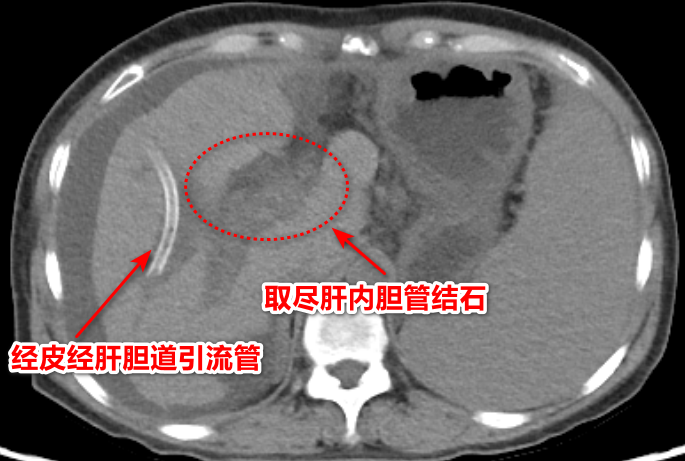

入院检查结果显示:肝内胆管弥漫性结石! 更棘手的是,结石不仅分布广,还藏在深层胆管,甚至合并了炎性狭窄。

影像检查显示

经过数次微创取石操作后,术后复查显示:肝内外胆管无结石残留。

术后兰女士的恢复迅速:次日即可下床活动,黄疸及炎症指标迅速下降。等到拔除经皮经肝胆道引流管后,兰女士顺利出院。